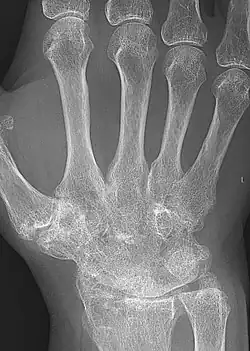

Ankyloza (gr. agkýlos ‘zakrzywiony’, ‘wygięty’)[1] – włókniste zesztywnienie[1][2] skutkujące unieruchomieniem[1] stawu powstałe najczęściej w wyniku reumatoidalnego zapalenia stawów (RZS)[2], urazu, zabiegu operacyjnego lub niektórych chorób kości i stawów[1].